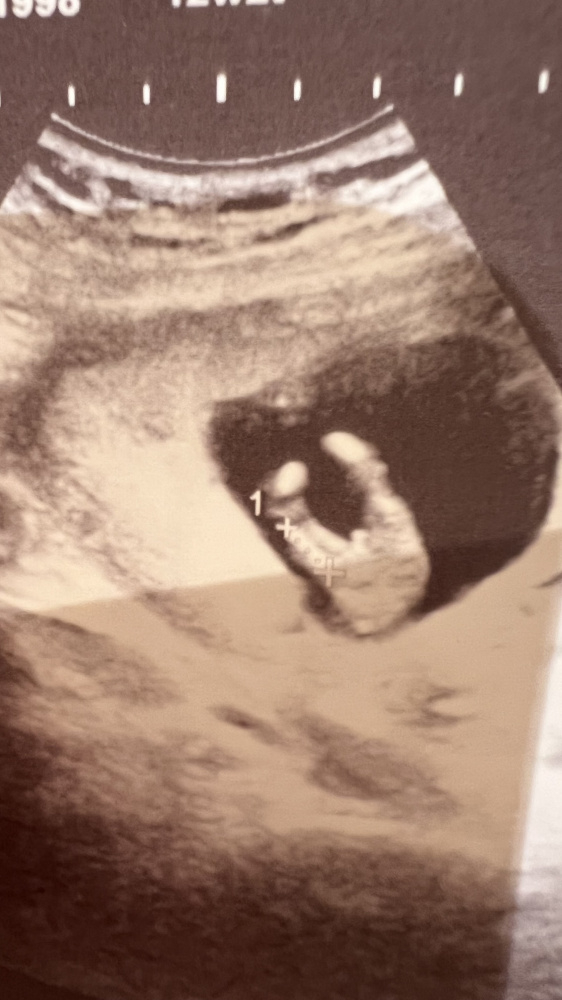

Hallo ihr Lieben,

ich bin neu hier aber habe die letzten Wochen bei euch still mitgelesen 🙈

Ich bin 13+2 und wollte fragen ob jemand von euch hier was erkennen könnte falls was zu erkennen gibt 😂